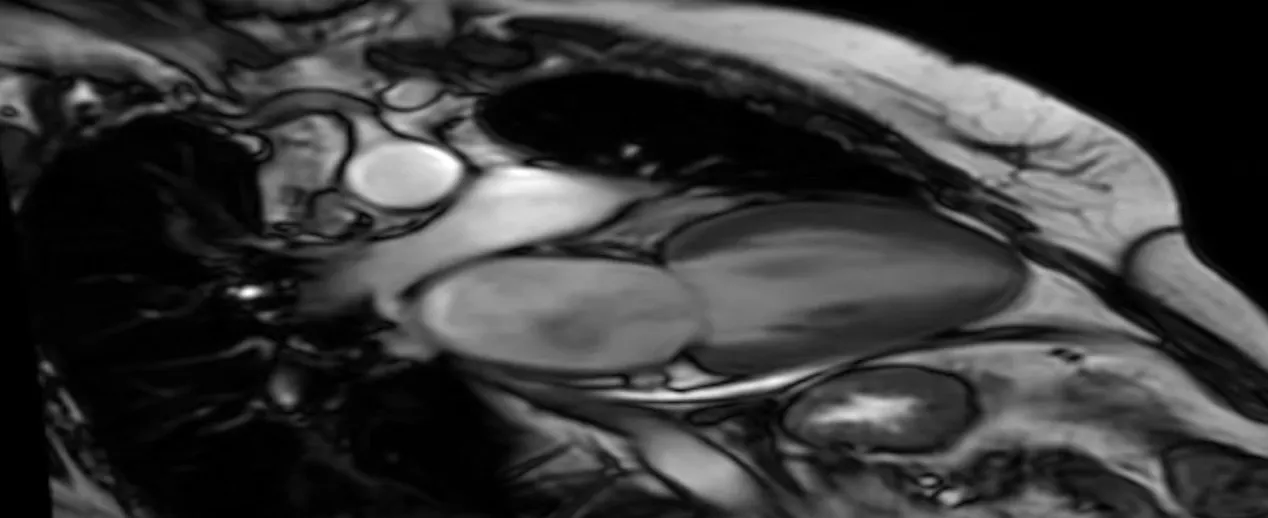

Somos referência em diagnóstico por imagem, com exames como ultrassonografia (convencional, com doppler e 4D), tomografia computadorizada, mamografia, densitometria óssea, ecocardiograma e raios-X. Também oferecemos consultas médicas nas especialidades de Gastroenterologia e Urologia.

Estamos dobrando o espaço físico da clínica para receber novos consultórios, exames inéditos na cidade e a aguardada ressonância magnética, fortalecendo nosso compromisso com a saúde e o desenvolvimento de Garça.